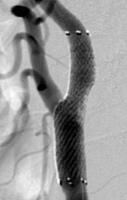

頸動脈ステント留置術

術後

狭くなり血流が悪くなってしまった頸動脈に、ステントと呼ばれる金属性のメッシュ状の筒を留置して血管を拡張させ、血流を回復させる手術です。